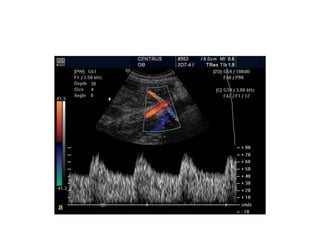

Figure 7 (a,b): Color flow imaging: effects of (PRF) or (scale) is set low

optimum level {11.0} (yellow arrow). The color image shows ambiguity within

the umbilical artery and vein and there is extraneous noise.